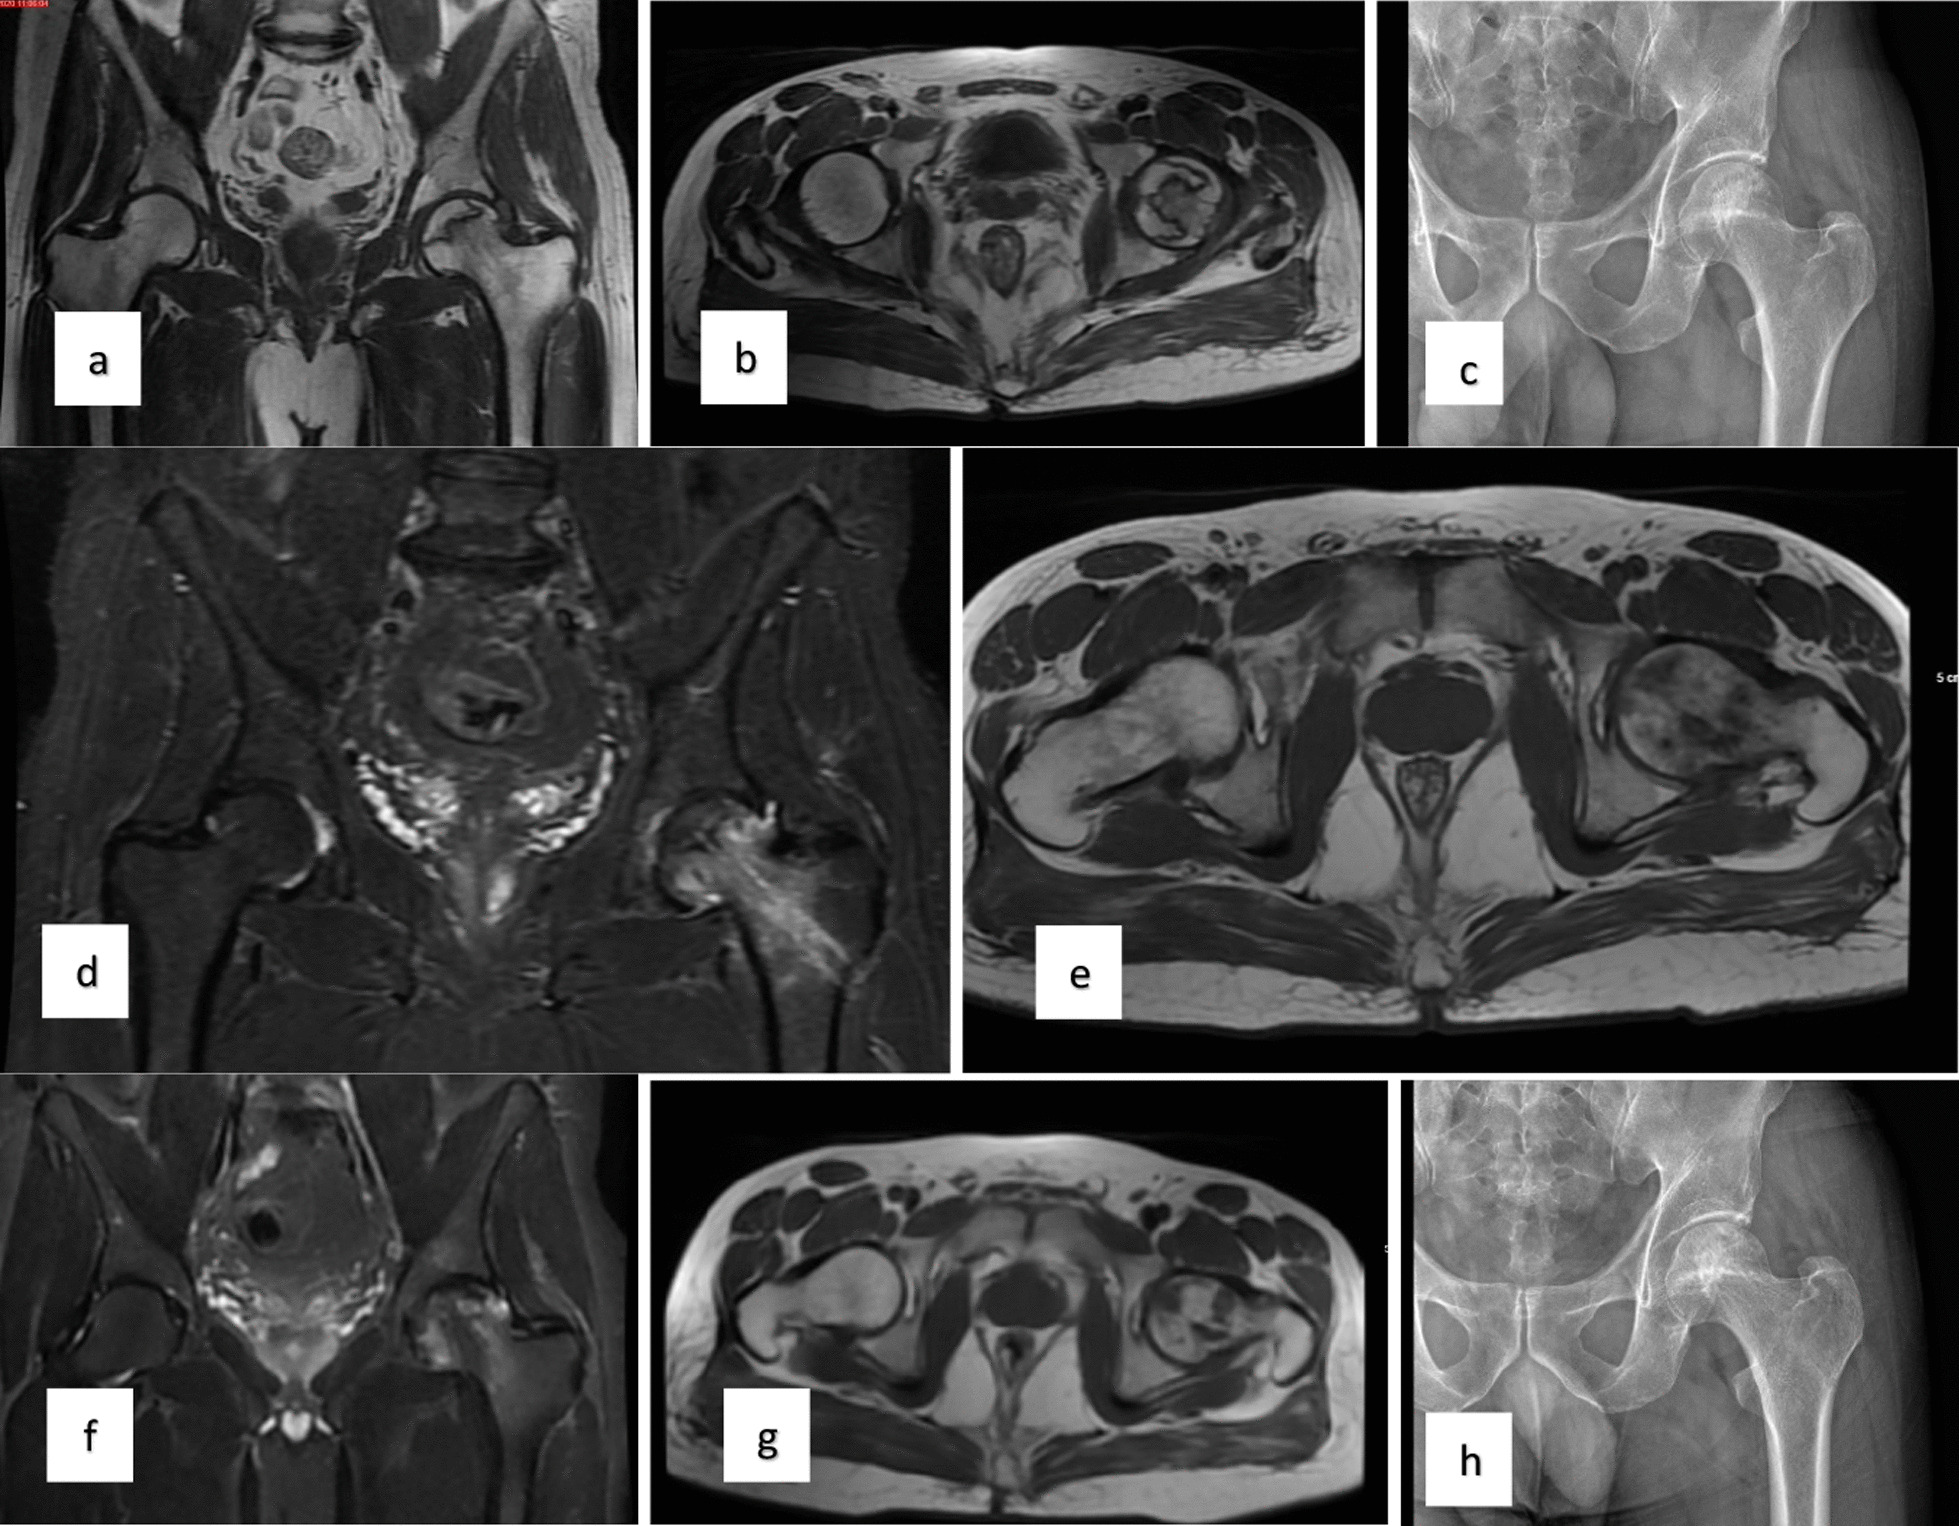

對(duì)患者的術(shù)前、3個(gè)月、6個(gè)月、1年和2年隨訪進(jìn)行評(píng)估(圖1)。

當(dāng)評(píng)估第1組和第2組的VAS評(píng)分時(shí),得出結(jié)論:基線和第3個(gè)月的VAS評(píng)分相似;6、12、24個(gè)月時(shí)差異有統(tǒng)計(jì)學(xué)意義,第2組VAS評(píng)分明顯較低。比較各組患者的HHS時(shí)得出的結(jié)論是,基線評(píng)分相似,第2組在第24個(gè)月時(shí)有顯著改善。此外,兩組治療前后的HHS均顯著改善。第1組和第2組患者VAS評(píng)分變化見表1,HHS評(píng)分見表2(圖2)。